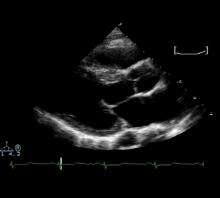

![]() Echocardiogram demonstrating systolic anterior motion of the anterior leaflet of the mitral valve |

A diagnosis of hypertrophic cardiomyopathy is based upon a number of features of the disease process. While there is use of echocardiography, cardiac catheterization, or cardiac MRI in the diagnosis of the disease, other important considerations include ECG, genetic testing (although not primarily used for diagnosis),[36] and any family history of HCM or unexplained sudden death in otherwise healthy individuals.

Generally, the diagnosis of HCM in a pediatric population is made during assessment for murmur, congestive heart failure, physical exhaustion, and genetic testing of children of affected individuals.[51] Specifically, echocardiogram (ECHO) has been used as a definitive noninvasive diagnostic tool in nearly all children. ECHO assesses cardiac ventricular size, wall thickness, systolic and diastolic function, and outflow obstruction. Thus, ECHO has been chosen as an ideal means to detect excessive wall thickening of cardiac muscle in HCM.[51]